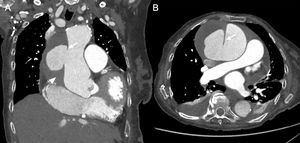

94-year-old woman admitted for congestive heart failure who, that morning, had developed chest and abdominal pain with paraesthesia in both lower limbs. Coronal (A) and axial (B) reconstructions of chest CT angiography to study pulmonary arteries for suspected pulmonary thromboembolism show a large pseudoaneurysm in the ascending thoracic aorta (arrow) and an adjacent mediastinal haematoma (arrowhead) containing the pseudoaneurysm.